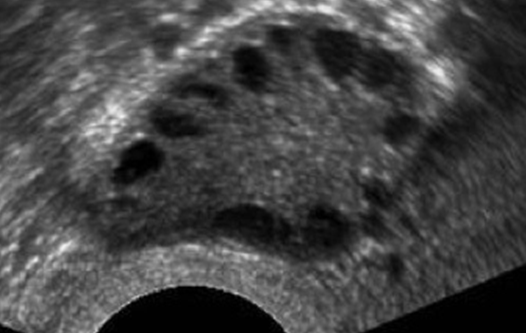

Weniger werden oder Ausbleiben der Regelblutung und/oder dem typischen Bild der Eierstöcke im Ultraschall, wobei die "Zysten" kleine Follikel (Eibläschen) sind und nicht - wie sonst üblich - zum Eisprung heranreifen, sondern alle in einem Frühstadium der Eizellreifung verharren. Insbesondere das Behaarungsmuster, oftmals auch das Übergewicht und/oder die Adipositas sind für Frauen sehr belastend. Wenn zwei der drei Symptome erfüllt sind, spricht man von einem PCO-Syndrom.

Im Ultraschall sieht man dann das typische Bild der polyzystischen Ovarien: